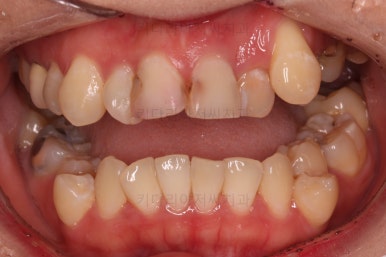

오늘 부산교정 키다리아저씨치과에서 소개해 드릴 환자분은 덧니, 치아상실(결손), 충치 등 많은 치과적 문제가 복합되어 있었던 분으로 충치치료 + 교정치료 후에 앞니 심미보철까지 진행했던 환자분입니다.

초진 시 입안의 모습입니다.

이미 썩어서 부러진 치아도 몇 개 보이고요.

많이 삐뚤어진 치아쪽은 양치가 힘들어 이미 많이 썩어 있는 상태에 덧니쪽은 잇몸도 많이 내려간 상태였습니다.

다만, 삐뚤고 썩은 앞니 때문에 웃는 모습이 부자연스러우셨고요.

드러나는 치아/치열의 모습이 심미적이지 못하죠.